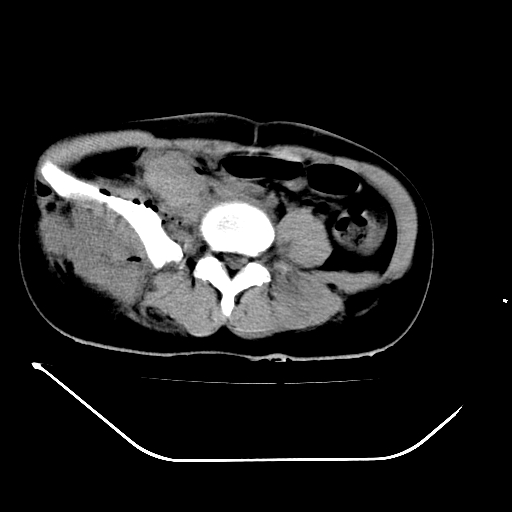

以下是引用liuyue在2008-7-19 13:02:00的发言:[br]1.肝右叶后下段及右肾挫裂伤伴腹腔积血。[br]2.右侧多发性肋骨骨折、横突骨折、右髂骨骨折伴周围软组织挫伤。[br]3.右侧腰大肌肿胀,并可见低密度影,如为气体,则肠道挫裂伤待除外。

以下是引用zhengfaming在2008-7-19 14:42:00的发言:[br]1.肝右叶后下段及右肾挫裂伤伴腹腔积血。脾脏挫裂伤待排[br]2.右侧多发性肋骨骨折、横突骨折、右髂骨骨折伴周围软组织挫伤。[br]3.右侧腰大肌肿胀,并可见低密度影,如为气体,则肠道挫裂伤待除外